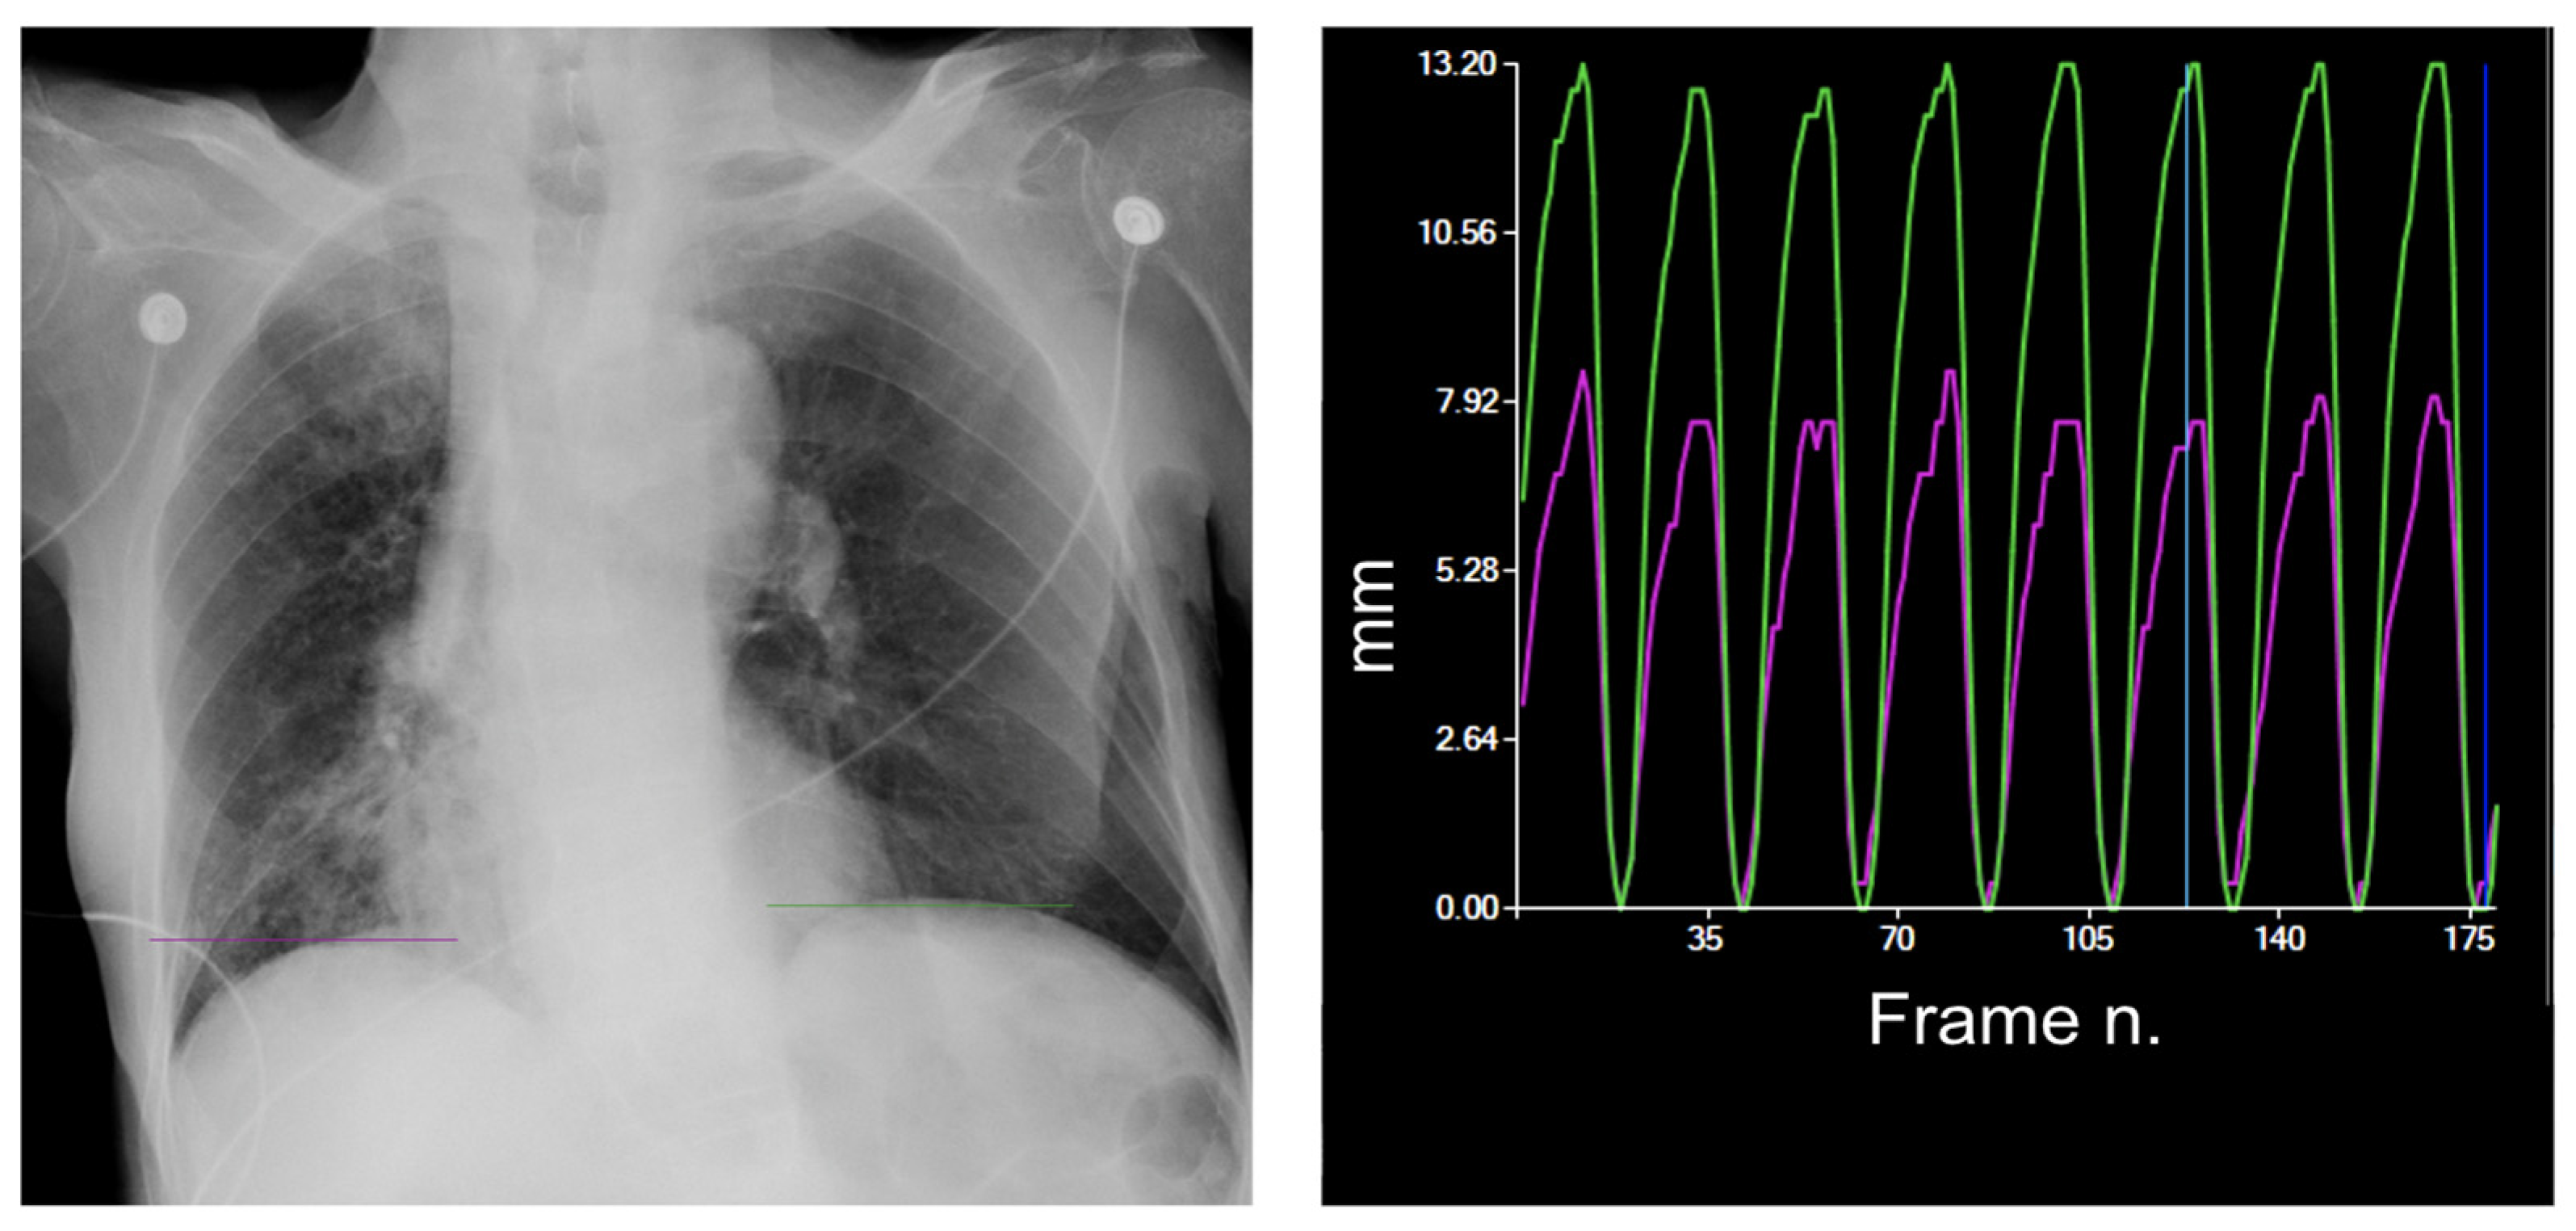

| DM-mode | Tracking diaphragm motion. Automatic calculation of the lung area and the relative changing rate (%). | Tracking of diaphragmatic domes represented in a motion–time graph. Area detection through an edge detection method in the post processing phase. | Diagnosis of diaphragm motion impairment and palsy. Automatic calculation of the respiratory rate. Analysis of lung dynamics in patients with restrictive/obstructive diseases. Follow-up of patients in pulmonary rehabilitation. |